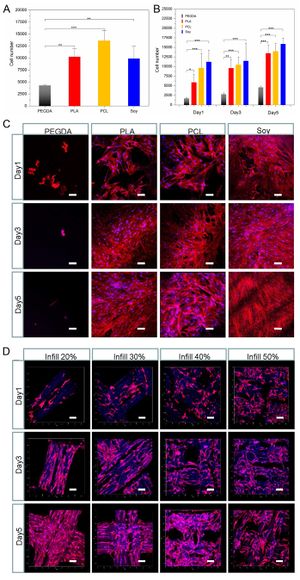

الطب الحيوي

قوة السحب الخلوي